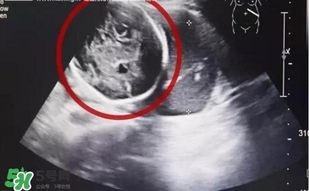

經(jīng)B超檢查,小芳竟然已經(jīng)懷孕了,而且胎兒已經(jīng)長(zhǎng)到了6個(gè)多月!但是讓人震驚的是胎兒并沒(méi)有長(zhǎng)在子宮里,而是長(zhǎng)在了腹腔內(nèi)。醫(yī)生確診小芳為“腹腔妊娠”,也就是宮外孕的一種,這種發(fā)病率約為1:15000,母體死亡率約為5%,胎兒存活率僅為1%的罕見(jiàn)妊娠,竟然發(fā)生在了她的身上,而且小芳已經(jīng)出現(xiàn)肚子疼痛,情況十分緊急!